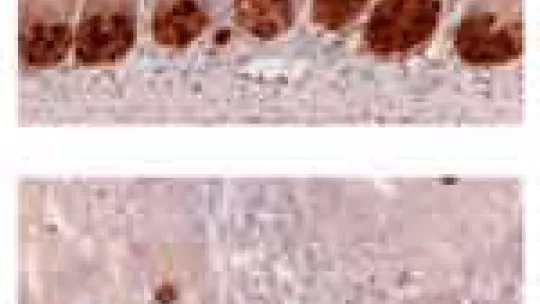

Los tejidos y órganos complejos necesitan separar en zonas distintas sus diferentes tipos celulares para mantener su arquitectura. En el caso del epitelio del intestino las células madre que regeneran el tejido se encuentran en el fondo de unas invaginaciones llamadas criptas, mientras que su progenie, las células diferenciadas que desarrollan las funciones de adsorción de nutrientes, se sitúan en la parte superficial.

Las proteínas denominadas receptores EphB, presentes en las células que residen en el fondo de las criptas, se unen a los ligandos Efrina localizados fundamentalmente en las células diferenciadas de la parte superficial del epitelio intestinal. La unión ligando-receptor ocurre en la frontera entre ambas poblaciones celulares y controla la posición de las células en el tejido. Sin embargo, hasta el momento no se conocía cómo estas uniones ligando-receptor ordenan a las células que se sitúen en un sitio u otro de la cripta.

Los resultados de este trabajo demuestran que las uniones EphB-efrina inducen la activación de la metaloproteasa ADAM10, que destruye las uniones entre tipos celulares distintos, como por ejemplo entre las células del fondo y de la superficie de las criptas. Es precisamente la destrucción de las uniones entre células de diferentes compartimentos lo que evita que se mezclen entre ellas, previniendo de esta forma que las células de un tipo penetren en el territorio equivocado y obligándolas a que se mantengan ordenadas en posiciones precisas dentro de las criptas. En palabras de Guiomar Solanas, primera autora del artículo, “hemos encontrado los mecanismos moleculares por los que los receptores EphB y sus ligandos efrina son capaces de decirle a cada célula dónde tiene que estar en cada momento de su vida: desde que se genera a partir de las células madre en el fondo de las cripta hasta que son células diferenciadas”.